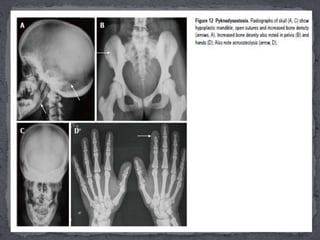

 Pycnodysostosis (PKND) is an autosomal recessive

disorder due to mutation involving cathepsin K gene

on locus 1q21.

 Age of presentation: They present early in childhood

with a triad of increased bone density, short limb

dwarfism and increased propensity for fractures.

 Essential radiological features:

 (1) Skull shows widely open sutures and fontanelles with

multiple wormian bones, mandibular hypoplasia with obtuse

angle and increased sclerosis of vault, base and orbital rims ;

 (2) There is increased bone density involving both limb bones

and pelvis . The limb length is decreased and pelvis is also small

with shallow acetabulae .

 (3) In hands, there is typically acro-osteolysis, i.e., resorption

 and tufting of terminal phalanges and

 (4)In limbs, medullary cavity is maintained while bowing of

radius and Madelung’s deformity can be occasionally seen.

 Other radiological features include hypoplasia of lateral ends of

clavicles similar to cleidocranial dysplasia, and occasional spool-

shaped vertebrae.